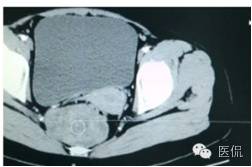

增强延迟期(CT值106HU)

手术是:盆腔占位,病理为:血管肌纤维母细胞瘤。与肛门粘连,于是同时做了肛门的处理。